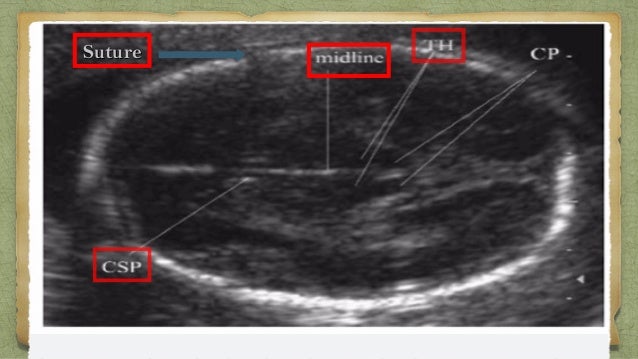

An NFT called Source Code for the WWW was sold on June 30 2021 for a winning bid of 5435500 What is NFT. With advances in technology and computer processing what was once a mere curiosity has become crucial for the assessment of the placenta membranes fluid and fetal anatomy as is covered in the other portions of this text. NFT was first measured on the standard horizontal transcerebellar images on which the midline structures were perpendicular to the ultrasound beam the horizontal image Figure 1.

It is 20 times longer Ch7 p111 Q4 More coiled cords are less easily. What happens to pulse repetition period. NFT was then measured again after moving the transducer approximately 30 towards the fetal occiput while maintaining the appropriate intracranial landmarks Figure 2.

The assignment of pregnancy age is the first task placed before the care provider and ultrasound. Figure 210 A and B. Assessed and reported on a routine 2 nd-trimester scan or when growth reassessment is required in the second or third trimester.